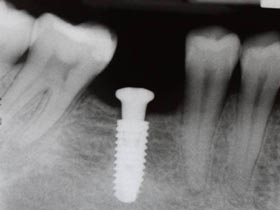

人工植牙

植牙致勝7部曲 牙齒永保安康 僅供參考

20100812法式微創植牙~龍霖醫師

2010-08-12